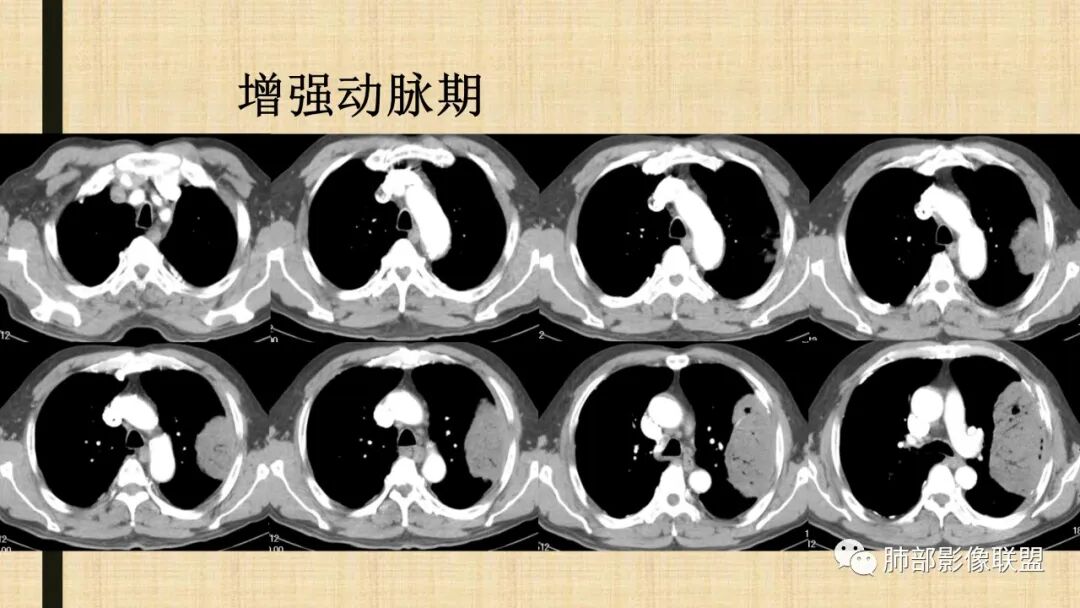

谢加平:

左肺上叶大肿块,膨胀性生长,边界清,密度较低,见部分坏死区,强化弱,肿块见支气管充气V扩张征,分布僵直,枯树枝特点,另一个重要特点血管造影征,淋巴瘤,肿块长轴与胸膜平行,与隐球菌鉴别,隐球荚膜抗原检查,明确诊断经皮肺穿刺。另胸膜钙化(问诊既往有无患胸膜炎病史)。

如果粘液腺Ca,周边太干净了,不支持。

飞鹰行动:

老年男性,糖尿病病史,消瘦、乏力三个月,影像表现左肺上叶胸膜下团块,有一定张力,内部疏松,可见支气管影及坏死区,增强病灶边缘环形强化,内部未见强化,考虑炎性肉芽肿病变,隐球?奴卡?放线菌?鉴别淋巴瘤。

宇宙:

左肺上叶胸膜下肿块,宽基底与胸膜相连,跨叶裂,边缘清晰膨隆,其内支气管充气,部分扩张、僵直,无明显强化,血管造影征,考虑淋巴瘤,鉴别腺癌

秦化君:

增强没有强化,血管束正常,气管束有正常有扩张,内有空洞,考虑炎性病变,隐球?